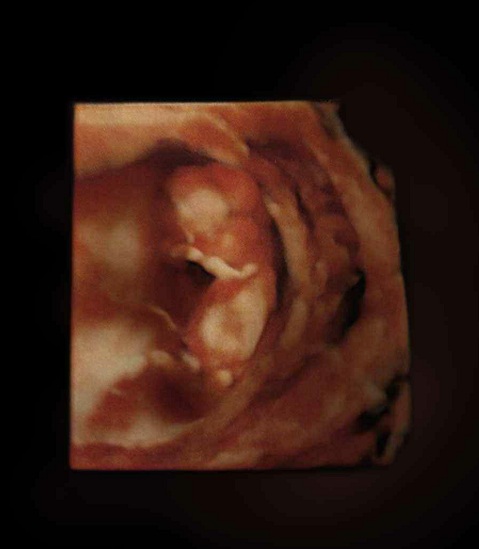

胎儿图

三维图

到本周末,你的胎儿的身长会达到38毫米,从形状和大小来说,都像一个扁豆荚。胎儿的体重大约10克。胎儿的眼皮开始粘合在一起,直到27周以后才能完全睁开。

他(她)的手腕已经成形,脚踝开始发育完成,手指和脚趾清晰可见,手臂更长而且肘部变得更加弯曲。现在,胎儿的耳朵的塑造工作已经完成,但是用B超还是分辨不清性别,现在胎儿的生殖器开始发育,胎盘已经很成熟,可以支持产生激素的大部分重要功能。